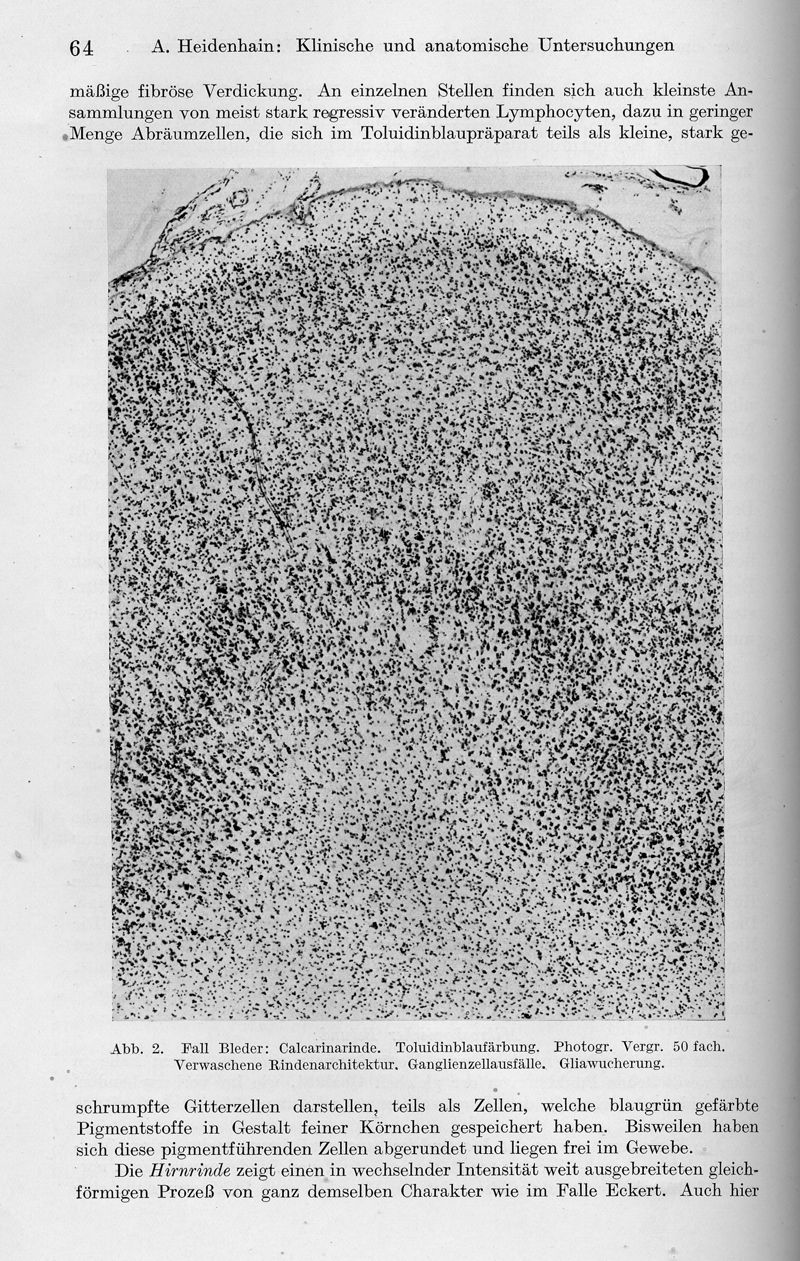

Klinische und anatomische Untersuchungen über eine eigenartige organische Erkrankung des Zentralnervensystems im Praesenium

In : Zeitschrift für die gesamte Neurologie und Psychiatrie, 1929, Vol. 118, pp. 49-114